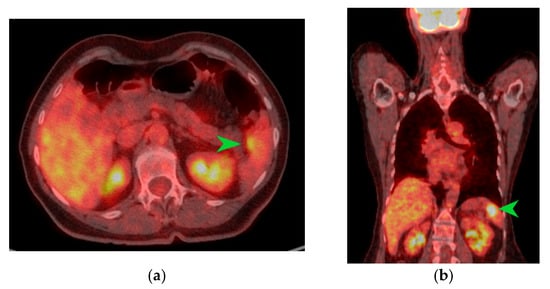

Figure 3.

PET-CT images in transverse (a) and coronal (b) sections highlighting an area of metabolic activity in the spleen that raises suspicion of splenic metastasis. The splenic tumor is indicated by the green arrow.

The macroscopic examination of the gastric resection specimen revealed a tumor ulceration of 3/2.5 cm (Figure 1a). Microscopic evaluation confirmed the presence of moderately differentiated intestinal-type gastric adenocarcinoma (G2), infiltrative in the subserosa, with vascular tumor emboli present (Figure 1b). Twenty-eight lymph nodes were identified, and tumor invasion was confirmed in five of them. The surgical resection margins were free of tumor invasion. Postoperatively, the patient remained under oncological follow-up, and approximately 10 months postoperatively, he reported significant weight loss and physical asthenia, symptoms that were initially considered to be associated with the complex treatment of the neoplastic disease. However, serum determination showed a slight increase in CEA to 6.5 ng/mL from 3.2 ng/mL and an increase in CA19-9 to 160 U/mL from 21 U/mL (Table 1), which led to the decision to perform an abdominal CT that revealed the presence of a hypodense, poorly iodophilic splenic lesion, measuring 23.5/16 mm, raising suspicion of a splenic metachronous metastasis (Figure 2). The imaging examination was continued with a PET-CT scan, which highlighted the pathological uptake of 18F-2-deoxy-2-fluoro-glucose (18F-FDG) at the level of the previously described lesions without detecting other areas of suspected metabolic hyperactivity (Figure 3).